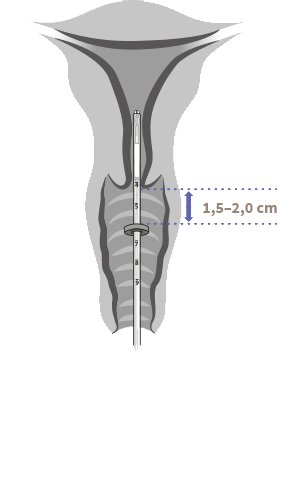

5. Før inn en uterinsonde i cervikalkanalen til fundus for å måle dybden og for å bekrefte livmorhulens retning, samt å utelukke eventuelle tegn på intrauterine misdannelser (f.eks. septum, submukøse myomer) eller et intrauterint prevensjonsmiddel som er satt inn tidligere og som ikke er tatt ut. Dersom innføringen er vanskelig, bør dilatasjon av kanalen vurderes. Hvis cervixdilatasjon er nødvendig, bør bruk av analgetika og/eller paracervikalblokk vurderes.

8 trinn for riktig plassering av Kyleena